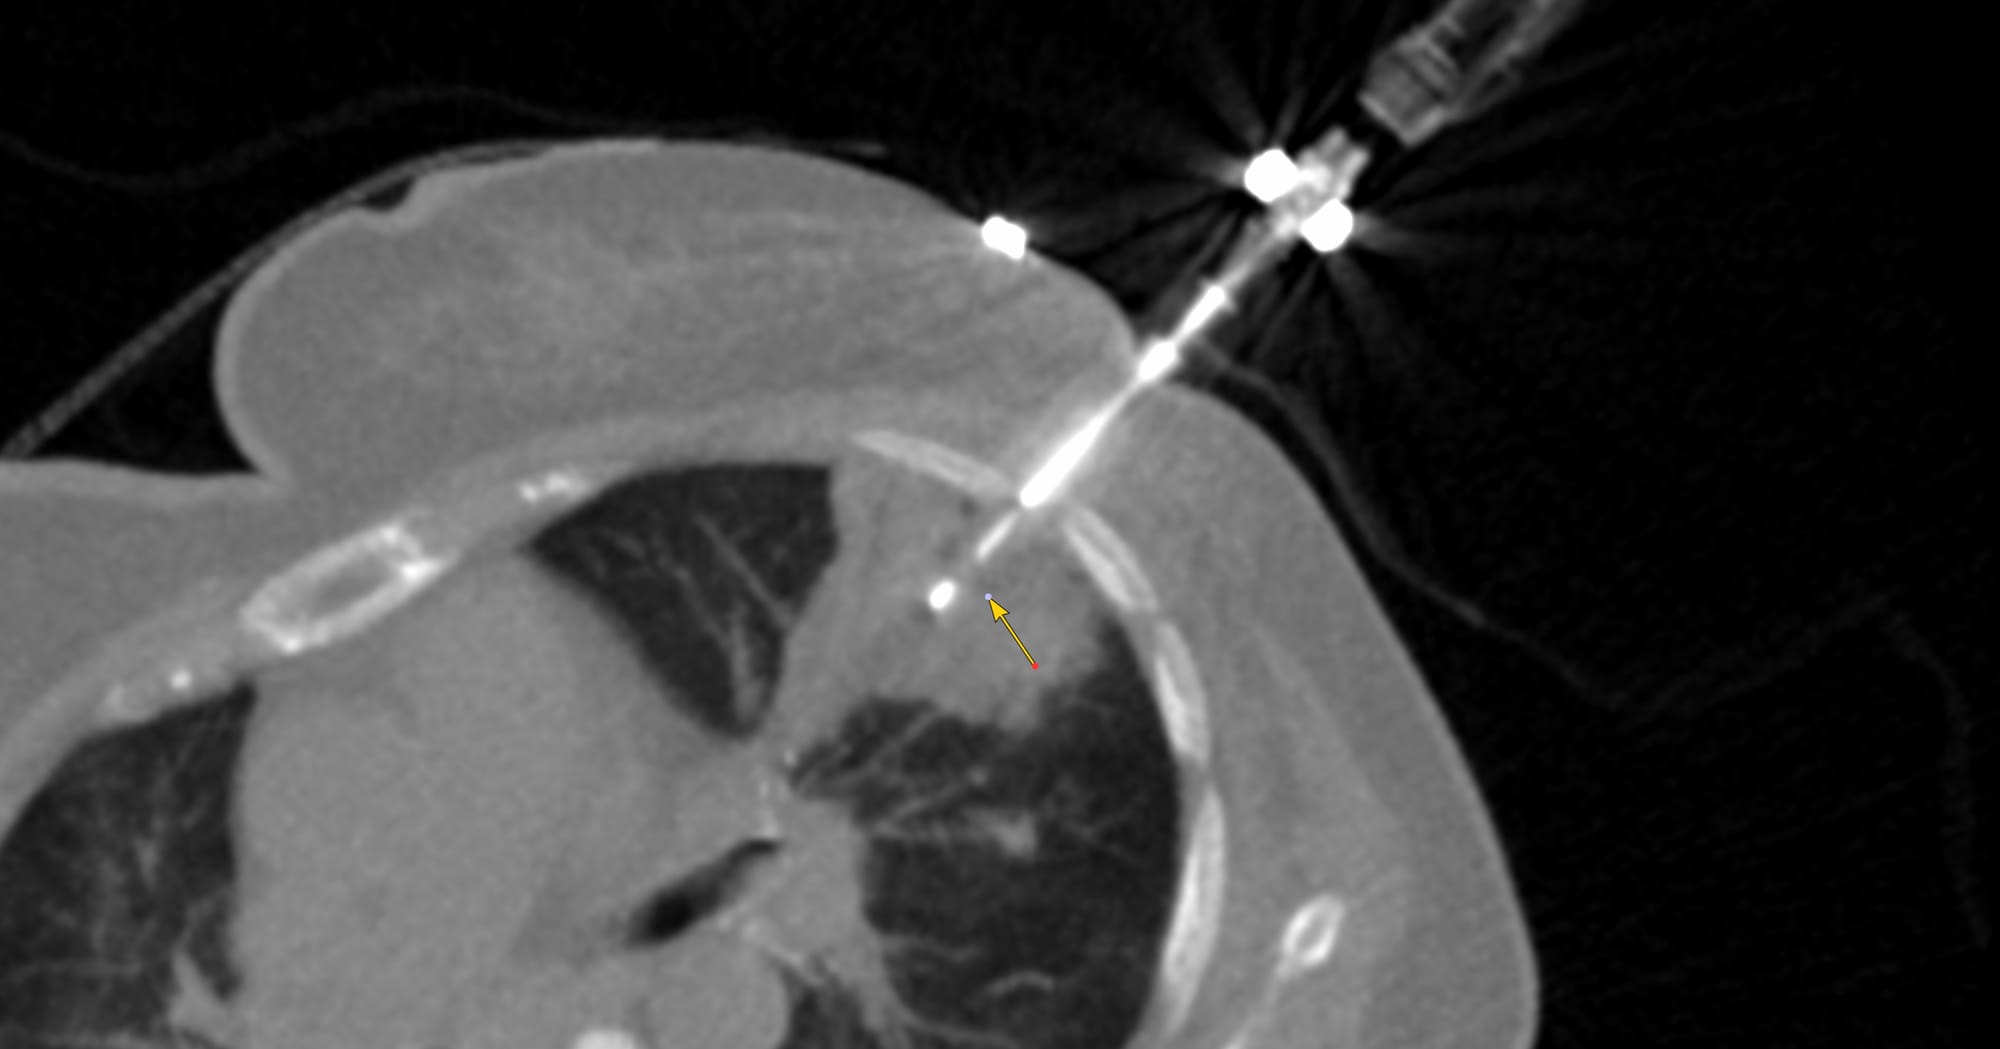

Case of the Day - 098 - 2025 09 08 - Confirming Tuberculosis of the Lower Cervical Spine

Bhavin Jankharia - 09 September 2025